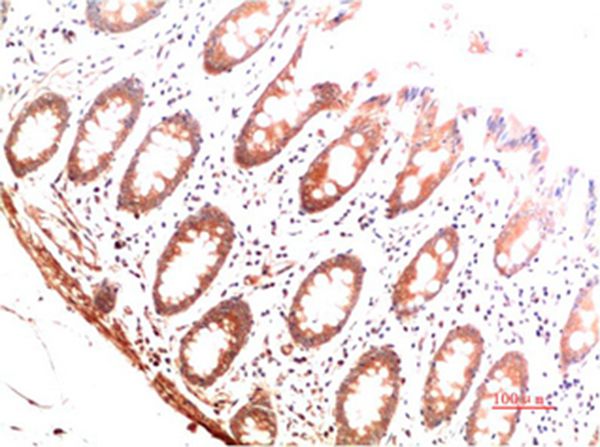

分类: 科研抗体货号: P43512别名: Collagen alpha-1(I) chain (Alpha-1 type I collagen)应用: IHC反应种属: Human,Mouse,Rat